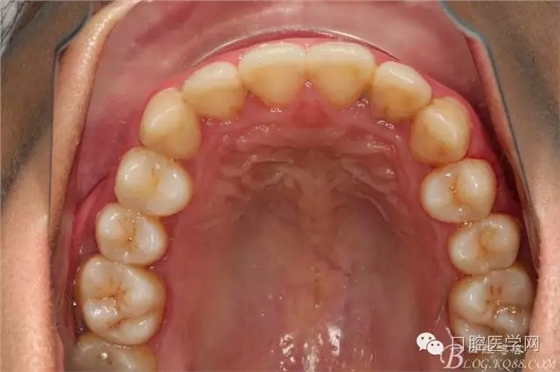

患者都是以刷牙出血為主訴。術(shù)前照片

術(shù)后照片